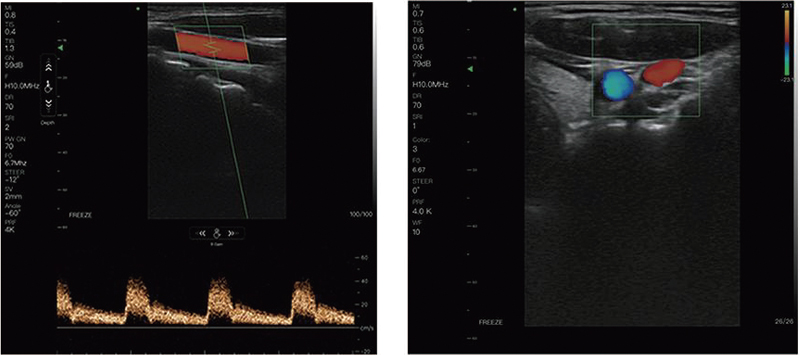

Application Sites: Abdomen, Superficial, Lung, Cardiac

- Scan Mode: B, B/M, Color, PW